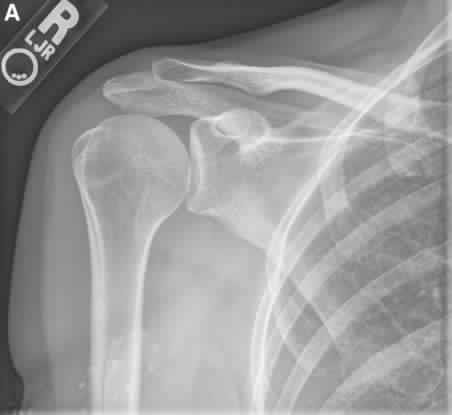

(OBQ15.201) A 52-year-old, right hand dominant man comes for evaluation of right shoulder pain that has been …